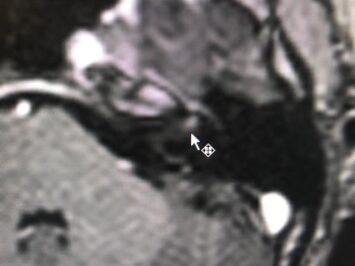

Caso: Neuritis del nervio facial izquierdo. RM cerebral.

Dra. Sterling Arróliga Selva

Lic Francisco Paseta.

Ing Lesther Lira.